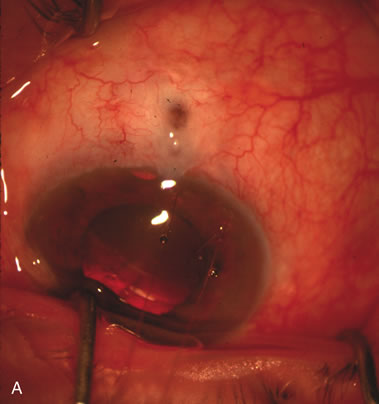

CASE 6: ANTICIPATED LENS EXTRACTION POST FAILED TRABECULECTOMY WITH ADVANCED DISC DAMAGE AND IOP OUTSIDE TARGET PRESSURE RANGE

The inflammation associated with lens extraction at any site usually causes complete failure of a marginal functioning bleb. In addition, pressure reduction by medical means is usually minimal in these recalcitrant cases, and combined surgery is indicated. In the past, these cases were approached with large-incision ECCE, clear corneal cataract incision, and bleb revision. Drawbacks included those mentioned earlier for large incision clear corneal cataract extraction, and bleb revision is often associated with conjunctival buttonholes, wound leaks, subconjunctival hematoma, destruction of friable sclera, and associated hypotony. With the advent of modern-day cataract surgery, a phacotrabeculectomy is often possible adjacent to the failed filter (Fig. 7). The ability to combine cataract extraction with implant and filtration surgery all through the same small incision has greatly improved outcomes for patients with marginal preoperative filters. There are several other viable options in this case. If the surgeon elects to remove the cataract through a temporal clear corneal incision, the bleb may be revised or a new adjacent filter fashioned. As mentioned earlier, revising a failed filter is technically challenging. If the surgeon believes it is not feasible to revise the filter or fashion a new one, a glaucoma drainage implant is a reasonable option combined with temporal lens extraction.172

Fig. 7. Phacotrabeculectomy adjacent to a failed filter in cataractous eye. The ability to combine small-incision cataract extraction with trabeculectomy all through the same incision adjacent to the failed filter allows the surgeon to work in a familiar superior area. Avoiding incisions into the existing bleb decreases conjunctival buttonholes, hypotony, operating room time, and subconjunctival bleeding. A. Appearance of failed bleb with exposure of superior temporal quadrant gained with a corneal traction suture. B. Prepare a limbus-based conjunctival flap and a scleral flap. C. This bleb is at high risk to fail again justifying the need for MMC, 0.2 mg/cc applied on a pledget for 4 minutes. D. Insert the keratome and perform phacotrabeculectomy in the usual fashion.